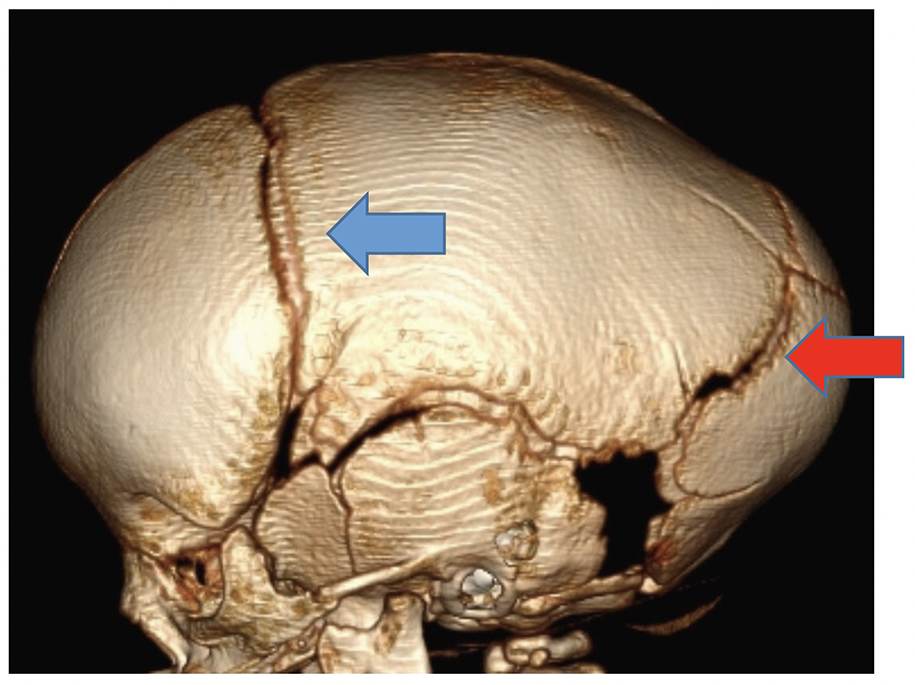

Craniosynostosis refers to the premature fusion or ossification of the cranial sutures and can occur from genetic etiologies, as well as from some metabolic disorders and mechanical changes, such as in a child with shunted hydrocephalus. With premature closure of a suture or sutures, relatively predictable head shapes and facial distortion occurs. A child with premature fusion of the sagittal suture, the most common type of craniosynostosis, presents with an elongated head shape, as the skull continues to grow along the lambdoid and coronal sutures (Fig. 2).

A child with unilateral coronal synostosis presents with flattening of the frontal region on the affected side, and the head shape becomes somewhat trapezoidal. On radiographs, a classic imaging finding is the “harlequin eye,” as the orbit remodels adjacent to the fused coronal suture (Fig 3).

Although radiographs and ultrasound can be used to assess the sutures, a 3D head CT readily demonstrates the normal sutures, the prematurely fused sutures, and allows the doctor to consider different treatment options. At Cincinnati Children’s, these CTs are performed with a slightly lower radiation dose, as the bones are the primary interest, and multiplanar and 3D reconstructions are computer generated without any additional imaging or radiation exposure to the infant or child.